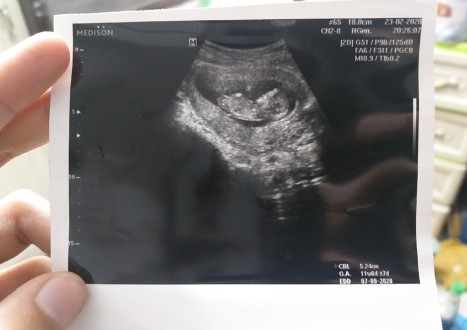

12+4 จ้า